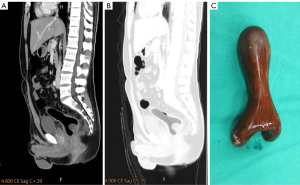

Laboratory investigations indicated mild leukocytosis (11,000/µL), and subsequent abdominal CT revealed no evidence of bowel wall thickening, pericolonic fat stranding, or fluid collection, suggesting no acute inflammation or perforation was present (Figure 2A). An abnormal low-absorption image (air-like image) was observed, although the foreign body could not be clearly identified within the colon.

However, upon adjustment to lung window settings, a radiolucent hypodense foreign body measuring nearly 10 cm in length was identified in the rectum and sigmoid colon with a window level ranging from −270 to −300 Hounsfield units (Figure 2B).

Consequently, a proctologist was consulted, and an emergent flexible sigmoidoscopy was performed, in which the foreign body was grasped with a flexible sigmoidoscope and a large endoscopic retrieval snare and extracted transanally. The foreign body measured 11.5 cm in the greatest dimension (Figure 2C). Successful removal of the object was achieved without complications.